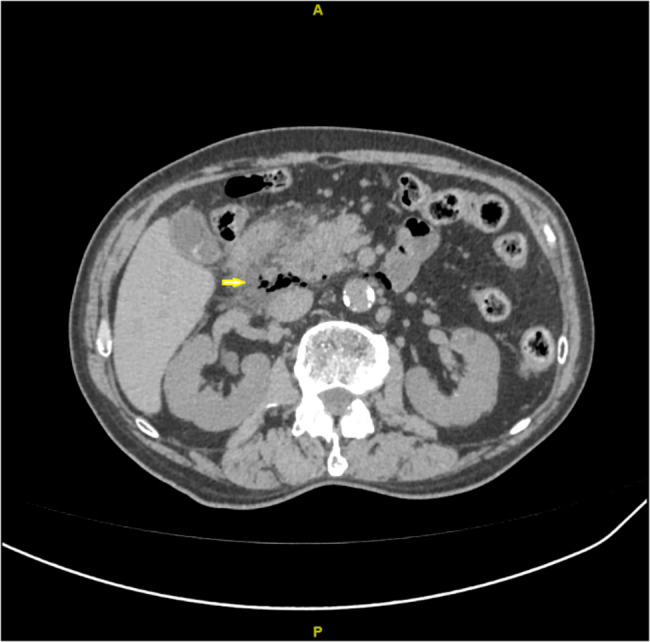

Presentation of case: A 78-year-old Chinese male patient presented with epigastric pain after overeating the day before admission. A contrast-enhanced computed tomography (CT) of the abdomen revealed cystic areas of extraluminal air in the posterior periduodenal area. We operated on the patient. A De Pezzer catheter and a nasogastric tube were placed in the duodenal cavity, supplemented by two external drainage tubes. Early postoperative enteral nutrition was facilitated through a jejunal feeding tube. The patient underwent successful surgical intervention and was discharged on the 12th post-operative day without any complications.